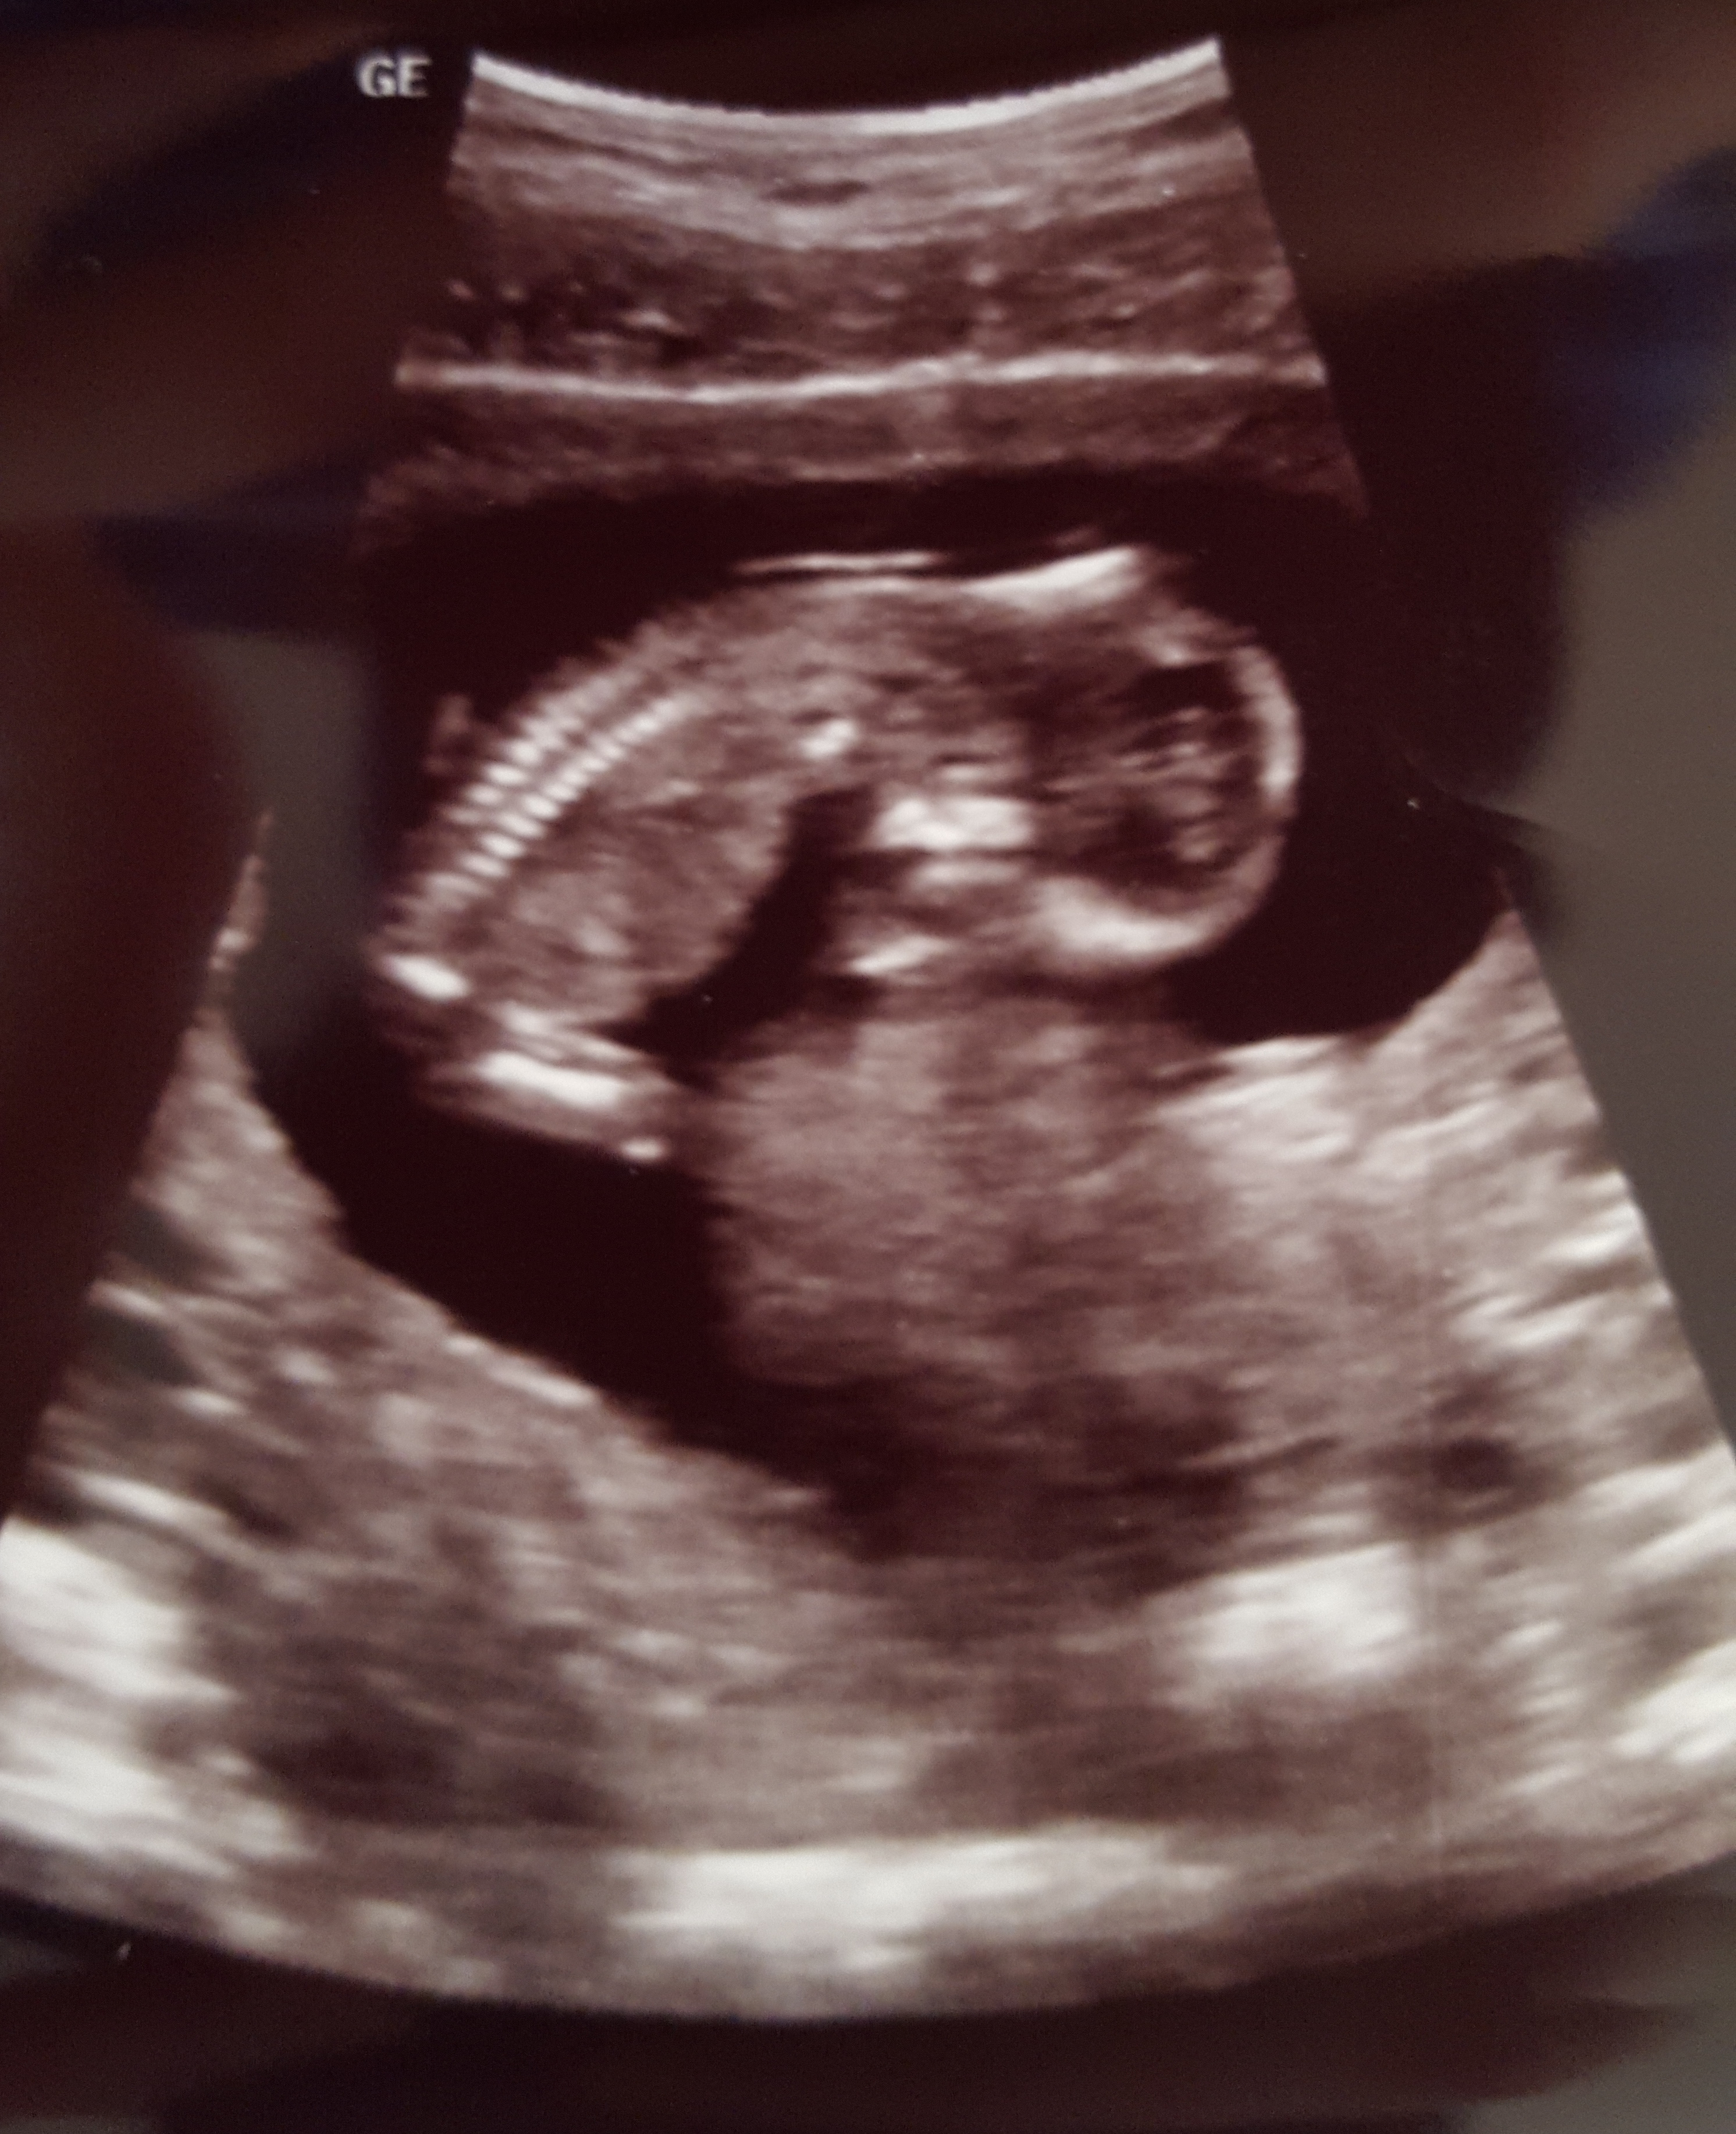

Here is my sweet little boy (we got our all clear Panorama results back today) at 12 weeks 4 days (yep, the due date moved up)! Heartbeat was 167 and he was a happy, wiggly worm. I've been bumped into March, so I wanted to wish you all the best.

Had my second sonogram today! 12+4 and he/she was moving around like crazy. At first it was laying on its side, so they told me to cough a couple times and doing that made it move onto its back. It's a neat trick they said works every time.

2nd ultrasound yesterday! First one was at 6 w 4 d and this one was at 12 w 4 d! Baby is measuring right smack dab on as far as dating and NT scan looked normal! Saw baby moving its hands and crossing its legs- loved it especially with all the bleeding and spotting scares we had this trimester!!